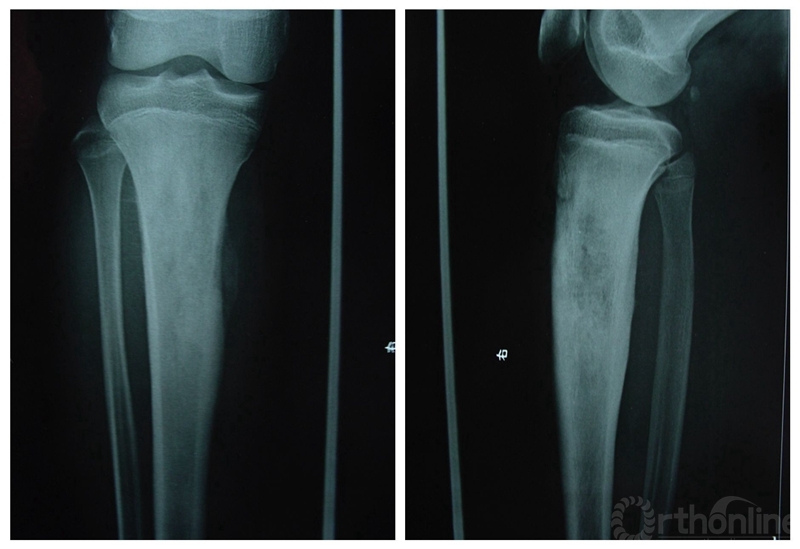

X线表现为侵袭性,破坏性和渗透性病损,能产生骨或骨样组织。侵袭和破坏区的特征为X线透亮,分界不清楚,很快会破坏皮质骨,进入软组织,但较少会跨越骨骺板和骨骺,进入关节腔(图1)。在皮质骨穿透区,可见反应骨的Codman三角,而病损边缘一般无反应骨。病变的其他部位不完全矿化,有不定形的非应力定向的瘤性骨。当新生骨与长骨纵轴呈直角时,呈“日光放射线”状,以前曾被认定是骨肉瘤的独特表现。后发现在其他一些恶性肿瘤也可有此表现,因此,“日光放射线”并不是骨肉瘤的特有表现。

图1.典型的骨肉瘤X线表现